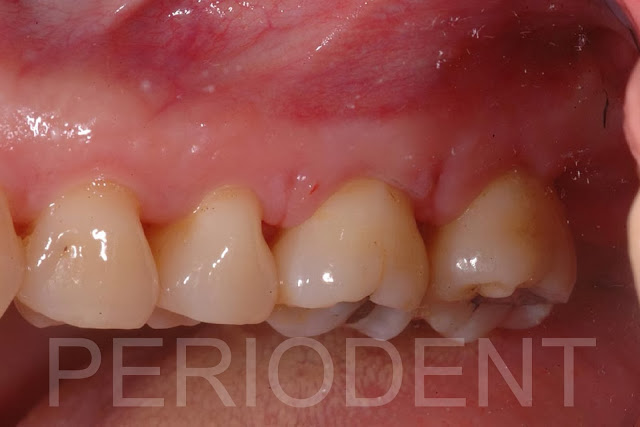

陳柏堅醫師發表上顎Distal Wedge手術之病例三